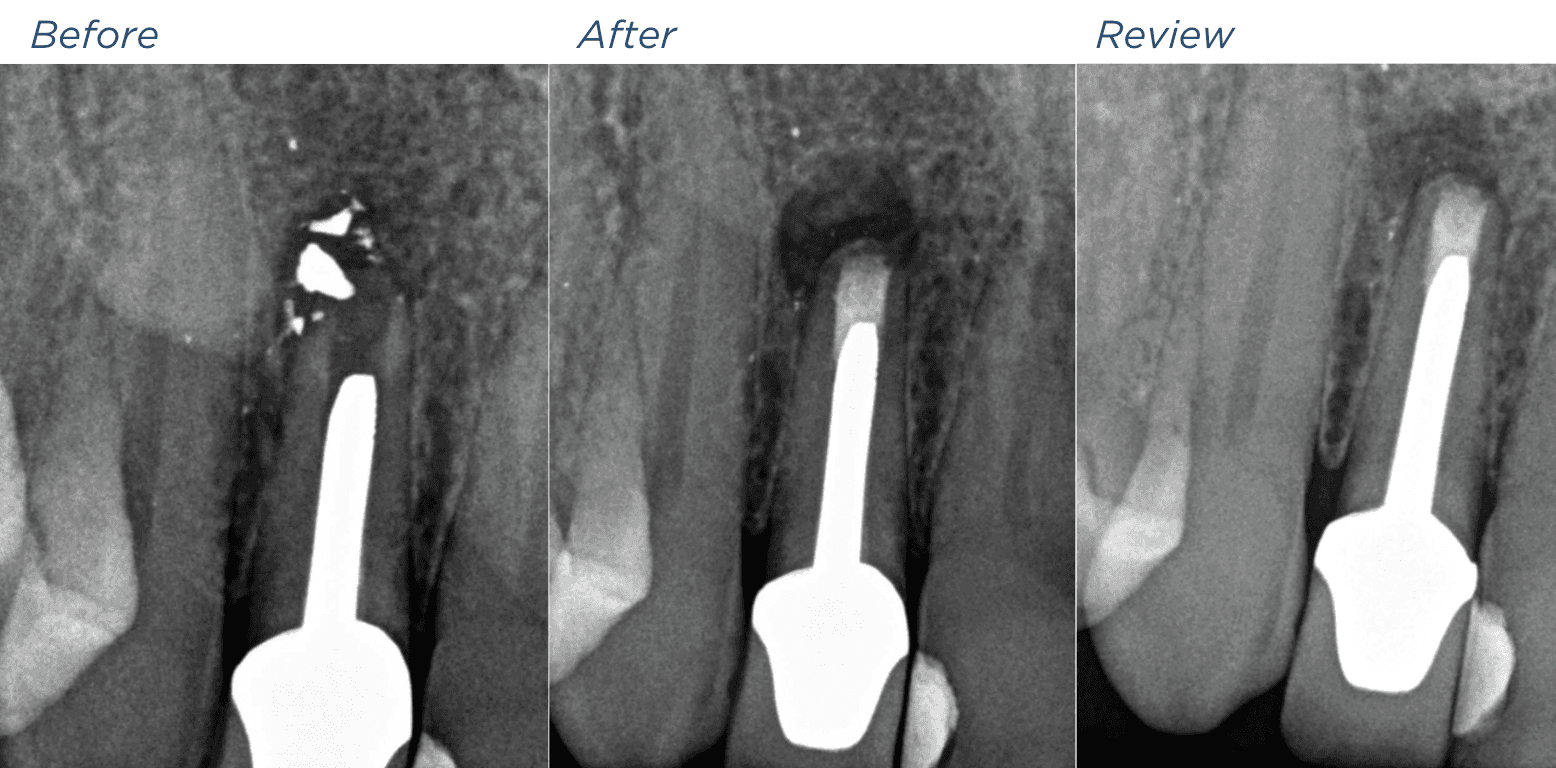

KREENA'S CASES